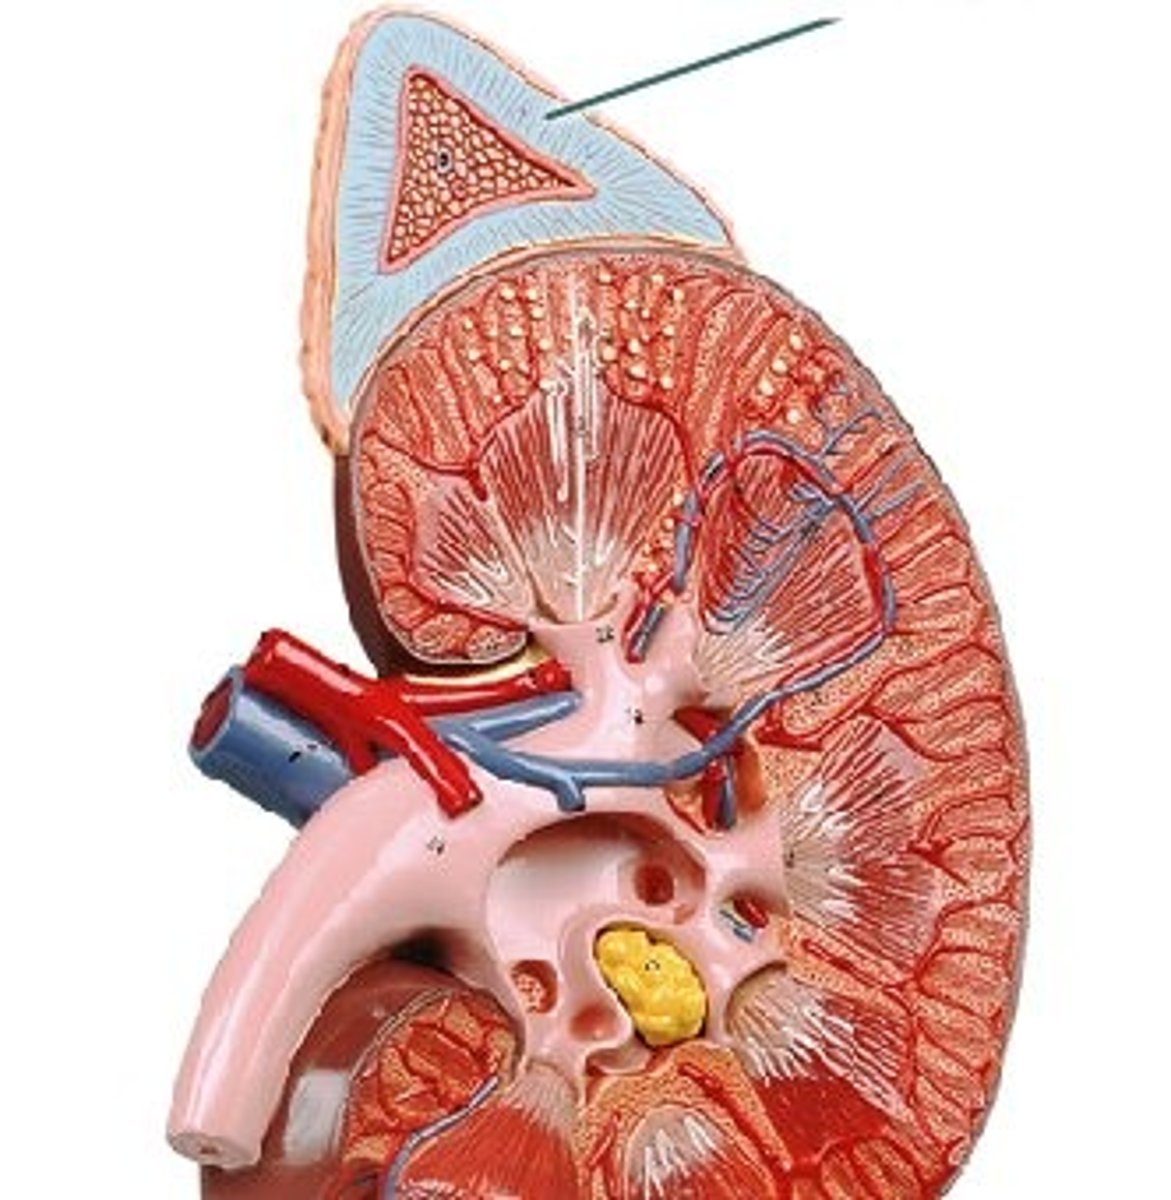

Erythropoietin (EPO)

Glycoprotein from the kidneys that stimulates red blood cell production in response to hypoxia.

Cholecalciferol

Vitamin D3 precursor produced by the skin; activated by kidneys to help absorb dietary calcium.